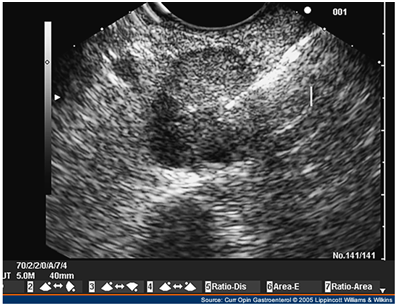

Endoscopic ultrasound

EUS allows the positioning of a high frequency (7.5-10 MHz) transducer in close proximity to the pancreas and lesions as small as 5 mm as well as tumors located in the bowel can be detected.

Although there is a potential "blind-spot" at the splenic hilum, a high sensitivity has been obtained. A recent single-centre prospective study showed a sensitivity of 93% and a specificity of 95% in localization of intra-pancreatic lesions. EUS could detect all tumors visualized by every other conventional technique, thus questioning the need for the rest imaging modalities (Figure 6–8).44–48

Figure 8 Linear endoscopic ultrasound image of a neuroendocrine tumor of the pancreas (insulinoma) undergoing fine needle aspiration. Note the rim-enhancing mass in the tail. 43